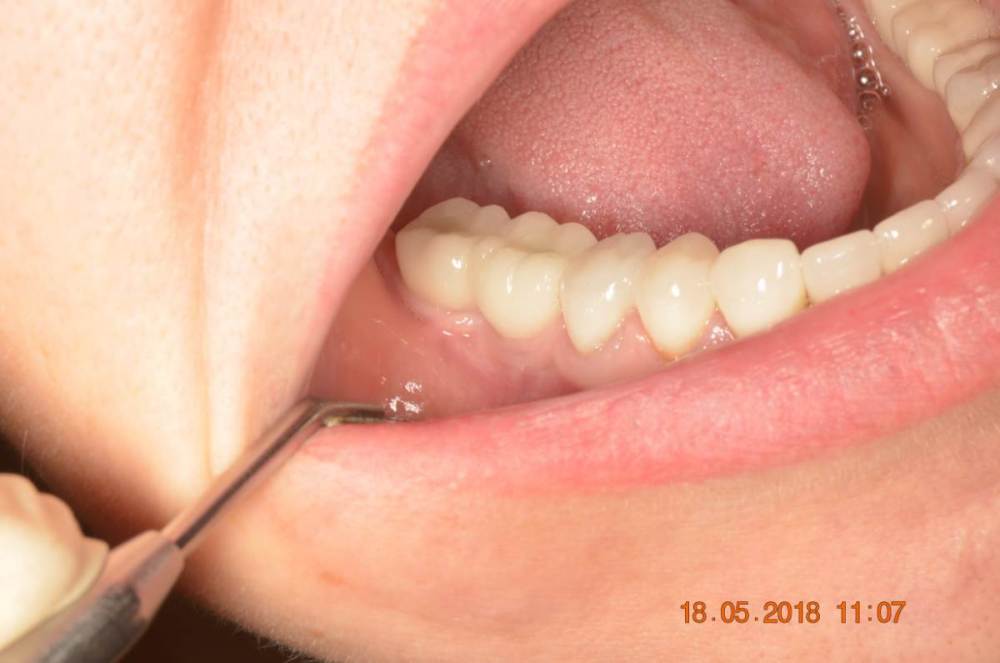

Большой Зеленый Опубликовано 15 августа, 2023 Поделиться Опубликовано 15 августа, 2023 Винтовая фиксация . 8 лет наблюдений .Полет нормальный. Немного прокрасились пломбы в шахтах. Пациентка довольна и счастлива. Привела уже вагон беззубых друзей и родственников. P/S. Система имплантов Ирис...:) 1 Ссылка на комментарий